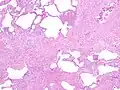

Appearance of usual interstitial pneumonia (UIP) in a surgical lung biopsy at low magnification. The tissue is stained with hematoxylin (purple dye) and eosin (pink dye) to make it visible. The pink areas in this picture represent lung fibrosis (collagen stains pink). Note the "patchwork" (quilt-like) pattern of the fibrosis.

Appearance of usual interstitial pneumonia (UIP) in a surgical lung biopsy at low magnification. The tissue is stained with hematoxylin (purple dye) and eosin (pink dye) to make it visible. The pink areas in this picture represent lung fibrosis (collagen stains pink). Note the "patchwork" (quilt-like) pattern of the fibrosis. Appearance of honeycomb change in a surgical lung biopsy at low magnification. The dilated spaces seen here are filled with mucin. Hematoxylin-eosin stain, low magnification.